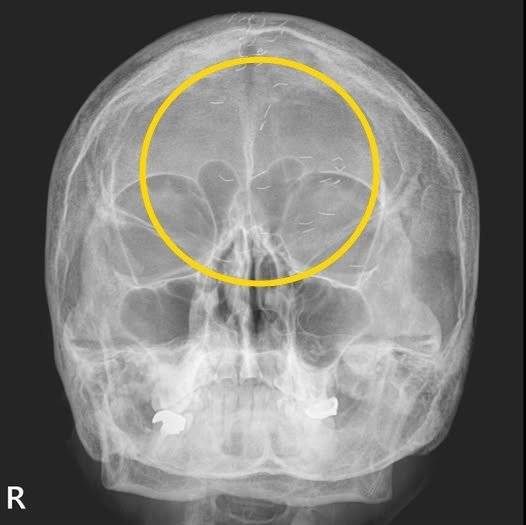

60대 한국여성의 머릿속에서 기생충처럼 보이는 이물질이 흩어져 있는 엑스레이 사진이 공개돼 화제다.

양 씨는 "엑스레이에서 1cm 크기의 다수의 이물질이 발견됐다"며 "기생충인가? 전기칩인가? 외국이었다면 특이한 환자 사례로 '케이스 리포트'에 올랐을 것"이라고 말했다.

양 씨는 “엑스레이에서 1cm 크기의 다수의 이물질이 발견됐다”며 “기생충인가? 전기칩인가? 외국이었다면 특이한 환자 사례로 ‘케이스 리포트’에 올랐을 것“이라고 말했다.

이어 “그러나 한국 의사들은 보자마자 헛웃음을 짓는다”며 “이물질의 정체는 ‘금침 요법’의 흔적”이라고 설명했다.

그러면서 “이물질이 무릎이나 허리에서 자주 발견되지만, 이번에는 머리에서 보였다”고 덧붙였다.

‘금침요법’은 금실매선요법을 말하는 것으로 얇은 순금을 1cm 미만의 길이로 자른 뒤 통증 부위에 주입하는 치료법이다. 침이 몸속에서 해당 부위에 지속적인 자극을 줘 치료 효과를 높인다고 하지만 이물질이 남아 염증 악화와 2차 감염 등의 부작용이 있을 수 있다.

양 씨가 금침요법을 무수히 받아온 환자에게 내린 진단은 ‘긴장성 두통’이었다. 환자는 양 씨에게 ‘머리 중앙이 자주 아파 침 치료를 받고, 신경과에서 MRI도 찍었지만 이상이 없었다’라고 전했다.